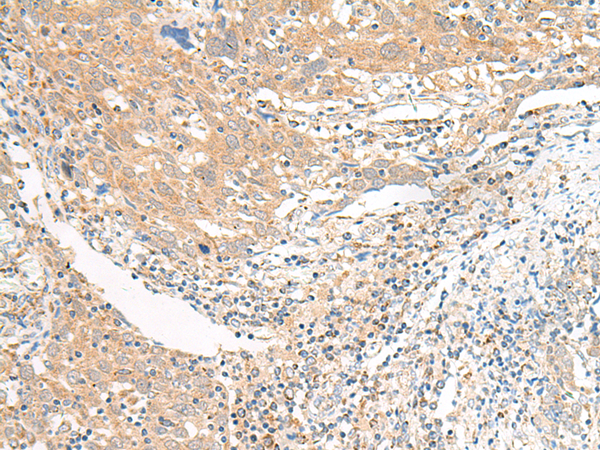

The image is immunohistochemistry of paraffin-embedded Human colorectal cancer tissue using 47583(SLC6A9 Antibody) at dilution 1/25.(Original magnification: 200)

The image is immunohistochemistry of paraffin-embedded Human cervical cancer tissue using 47583(SLC6A9 Antibody) at dilution 1/25.(Original magnification: 200)